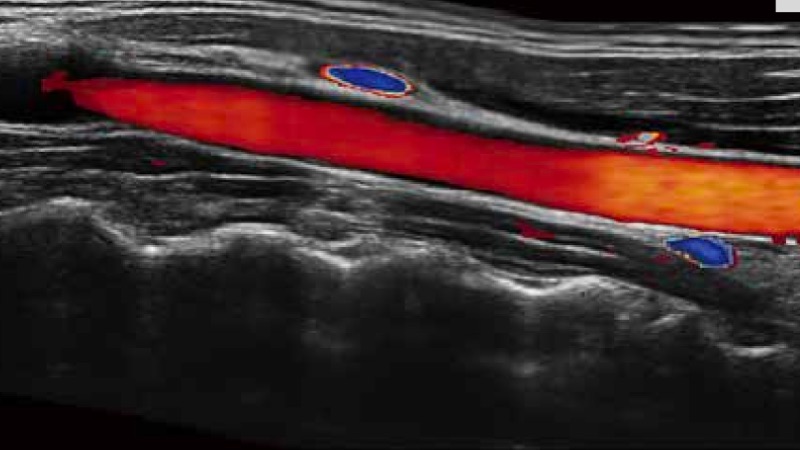

開立醫(yī)療通過不斷的技術(shù)創(chuàng)新,為大眾的生命健康提供持續(xù)關(guān)愛。P12 Plus采用全新一代超聲成像平臺,新平臺旨在將真實(shí)還原組織解剖結(jié)構(gòu)作為首要目標(biāo)。平臺采用全新集成化硬件模塊,搭載新一代芯片,系統(tǒng)性能得到大幅提升,為您的診斷提供了豐富的臨床信息。優(yōu)異的圖像表現(xiàn),豐富的探頭配置,全面的應(yīng)用功能,為您日常診斷提供了可靠的助手。